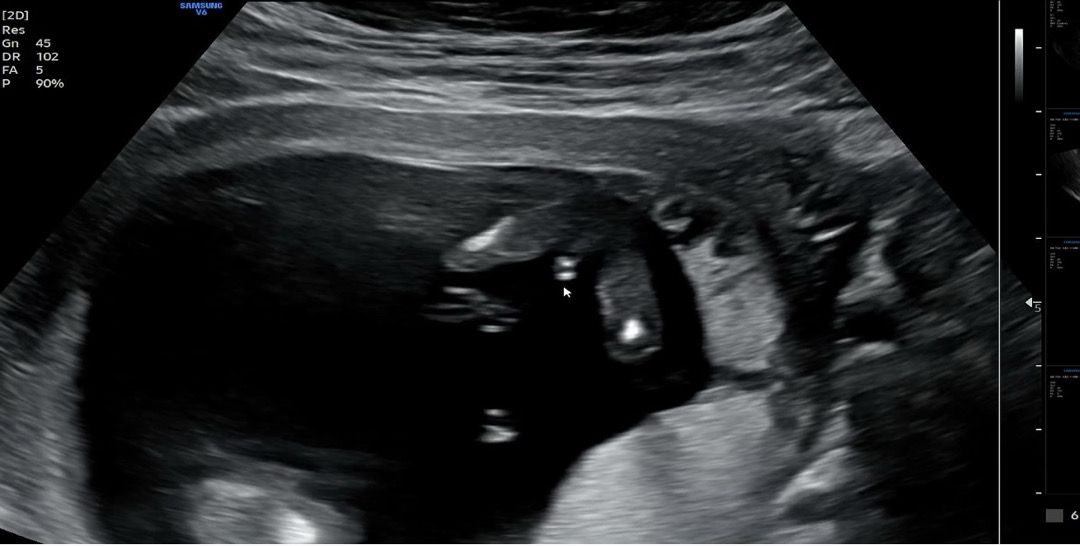

13주5일인데 초음파가…?

오늘 정기검진받으러 갔는데 의사쌤이 보고 웃으시더니 아직 성별 나올때가 아니라 뭐라고 말 할 순 없는데 너무 명확하게 뭐가 보인다고 웃으시는데 아들맘 확정인가요 이거?!ㅋㅋㅋㅋㅋㅋㅋㅋㅋㅋ

넹ㅋㅋㅋ아들같아요 ㅋㅋㅋㅋㅋ